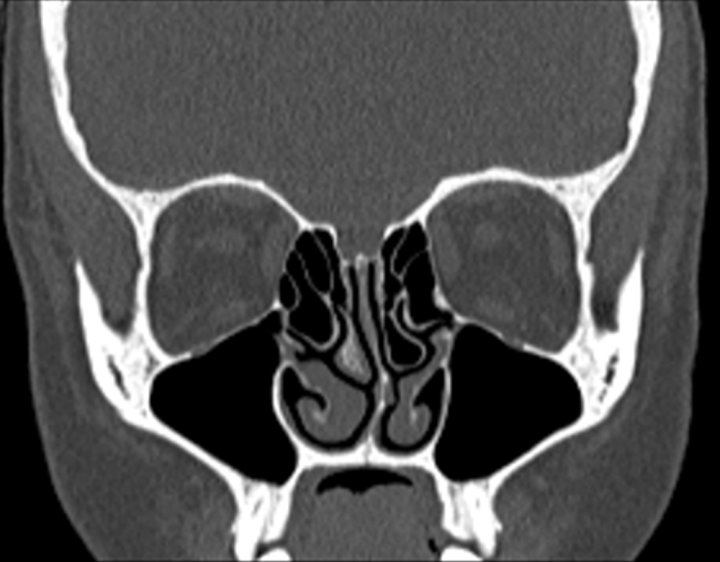

Click any image for labels.